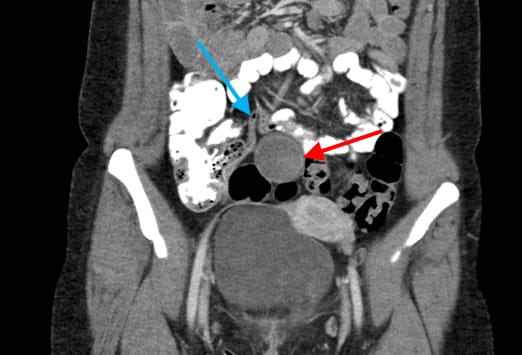

Diese 28-jährige Frau wurde mit seit 7 Tagen bestehenden, rechtsseitigen Unterbauchschmerzen vorstellig. Die zuvor für 15 Jahre durchgeführte Empfängnisverhütung hatte die Patienten vor einigen Monaten abgesetzt. In den letzten Monaten hatte sie rezidivierende Schmerzen im Bereich des rechten Unterbauchs. Im Bereich des Mittelbauchs kam eine zystische Struktur mit lokaler Akzentuierung zur Darstellung (roter Pfeil). Die Appendix zeigte sich unauffällig (blauer Pfeil).

Bei der zuvor beschriebenen Patientin wurde ein transvaginaler Ultraschall durchgeführt. Im Ultraschall ließ sich eine komplexe zystische Struktur im Bereich des rechten Ovars darstellen (links). Die Farbduplexsonographie ergab eine erhöhte periphere Durchblutung (rechts), vereinbar mit einer hämorrhagischen Corpus luteum Zyste. Es wurde eine erneute Verlaufskontrolle nach zwei Menstruationszyklen empfohlen.